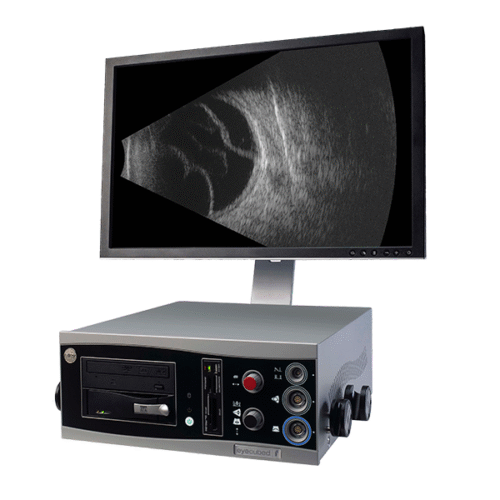

Choose Eye One™, and you can select from four scan modalities, which comprise:

- B-SCAN, 40MHZ UBM

- B-SCAN, 10 MHZ POSTERIOR

Low noise, high performance

In posterior B-Scan mode, Eye One’s industry leading signal-to-noise ratio means it’s able to detect the subtlest vitreous echoes, offering unparalleled distinction and diagnosis accuracy across the retina, choroid, sclera, and the vitreo retinal junction.

Every angle covered

In anterior wide-field mode, Eye One™ allows you to view the entire segment to identify causes of glaucoma-related disease, and to accurately and consistently measure key angle parameters.